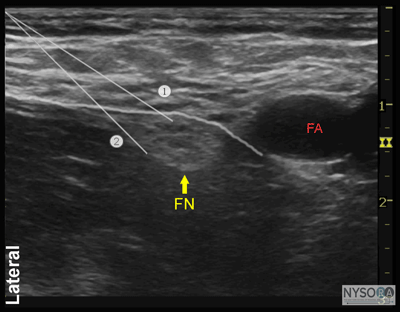

Figure 1: Transducer position and needle insertion using an in-plane technique to block the femoral nerve at the femoral crease. Essentials

![]() Figure 5: Transducer position and needle insertion using an in-plane technique to block the femoral nerve at the femoral crease. Technique With the patient in the supine position, the skin over the femoral crease is disinfected and the transducer is positioned to identify the femoral artery and/or nerve (Figure 4). If the nerve is not immediately apparent lateral to the artery, tilting the transducer proximally or distally often helps to image and highlight the nerve from the rest of the iliopsoas muscle and the more superficial adipose tissue. In doing so, an effort should be made to identify the iliopsoas muscle and its fascia as well as the fascia lata because injection underneath a wrong fascial sheath may not result in spread of the local anesthetic in the desired plane. Once the femoral nerve is identified, a skin wheal of local anesthetic is made on the lateral aspect of the thigh 1 cm away from the lateral edge of the transducer. The needle is inserted in-plane in a lateral-to-medial orientation and advanced toward the femoral nerve (Figure 5). If nerve stimulation is used (0.5 mA, 0.1 msec), the passage of the needle through the fascia iliaca and contact of the needle tip with the femoral nerve usually is associated with a motor response of the quadriceps muscle group. In addition, a needle passage through the fascia iliaca is often felt as a "pop" sensation. Once the needle tip is witnessed adjacent (either above, below, or lateral) to the nerve (Figure 6), and after careful aspiration, 1 to 2 mL of local anesthetic is injected to confirm the proper needle placement (Figure 7). When injection of the local anesthetic does not appear to result in a spread close to the femoral nerve, additional needle repositions and injections may be necessary. In an adult patient, 10 to 20 mL of local anesthetic is adequate for a successful block (Figure 8A and B).